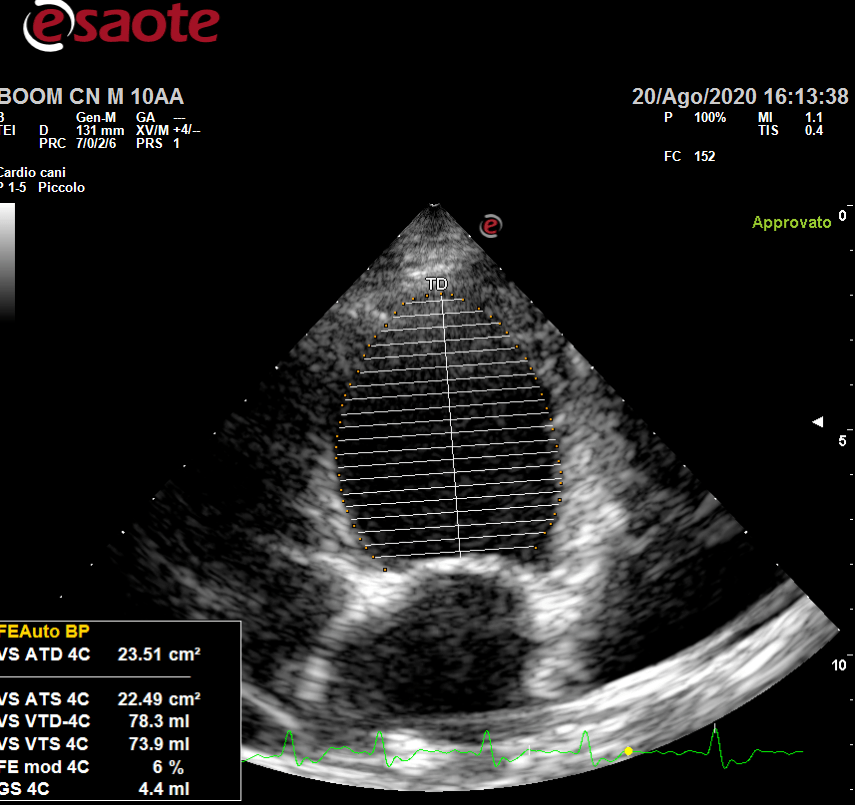

Effettuate tramite l’ecografo italiano Esaote My LabOmega, ecco quali sono le ecografie di cui ci occupiamo:

- ecocardiografie;

Cardiologia

- ecocardiografia specialistica, la quale consente di diagnosticare le cardiopatie presenti negli animali cardiopatici e di valutare la corretta terapia per ogni singolo animale;

- elettrocardiografia, ecodoppler per animali indispensabile per impostare terapie atte alla risoluzione delle cardiopatie quali mixomatosi della valvola mitrale, cardiomiopatia dilatativa;